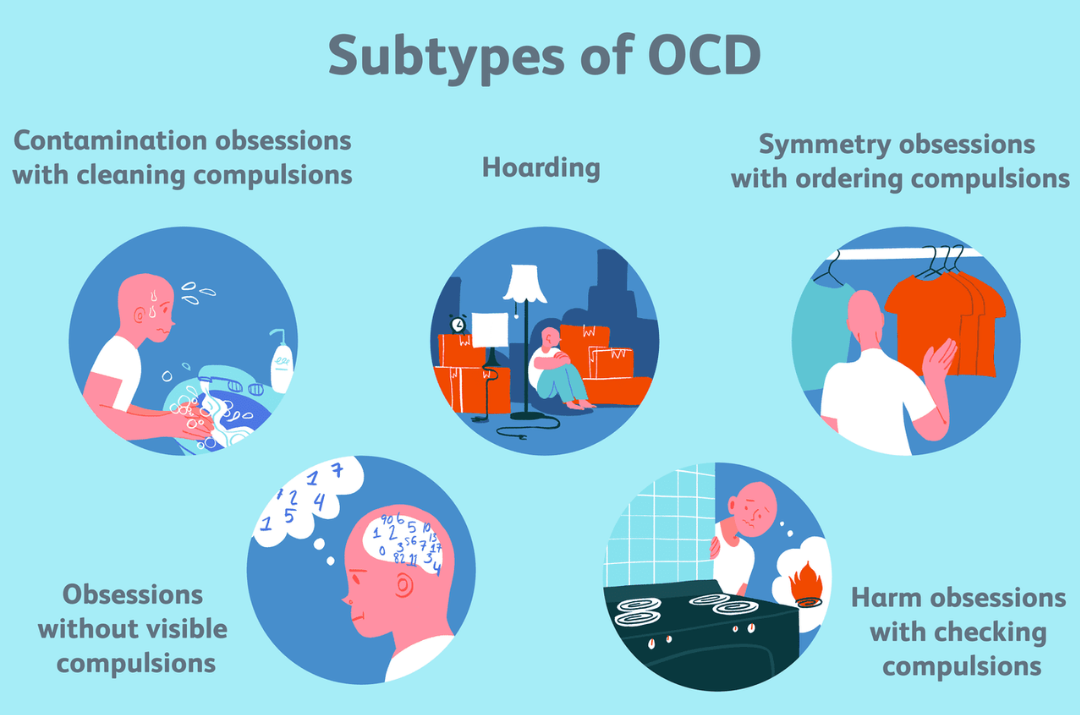

Disorders refer to abnormal conditions affecting physical or mental health, disrupting normal functioning. They can range from physical ailments like heart disease to psychological issues like anxiety. These conditions may be caused by genetics, environment, or lifestyle. Diagnosis often involves medical exams and tests. Treatment can include therapy, medication, or lifestyle changes to improve quality of life.

Disorders refer to abnormal conditions affecting physical or mental health, disrupting normal functioning. They can range from physical ailments like heart disease to psychological issues like anxiety. These conditions may be caused by genetics, environment, or lifestyle. Diagnosis often involves medical exams and tests. Treatment can include therapy, medication, or lifestyle changes to improve quality of life.